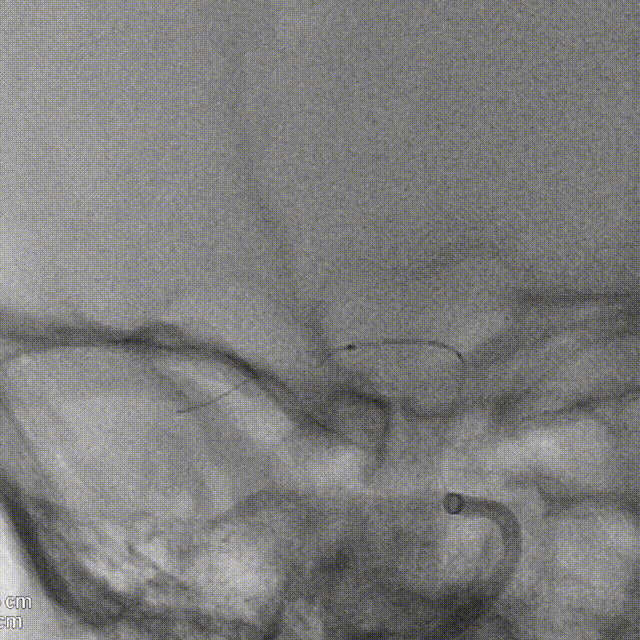

术后造影:支架覆盖两枚动脉瘤瘤颈,贴壁良好,瘤体内可见造影剂滞留。

术后支架显影:

术后造影:支架充分覆盖动脉瘤瘤颈,贴壁良好,瘤体内可见造影剂滞留。

术后支架显影:定位精准,未覆盖颞前动脉及大脑前动脉。